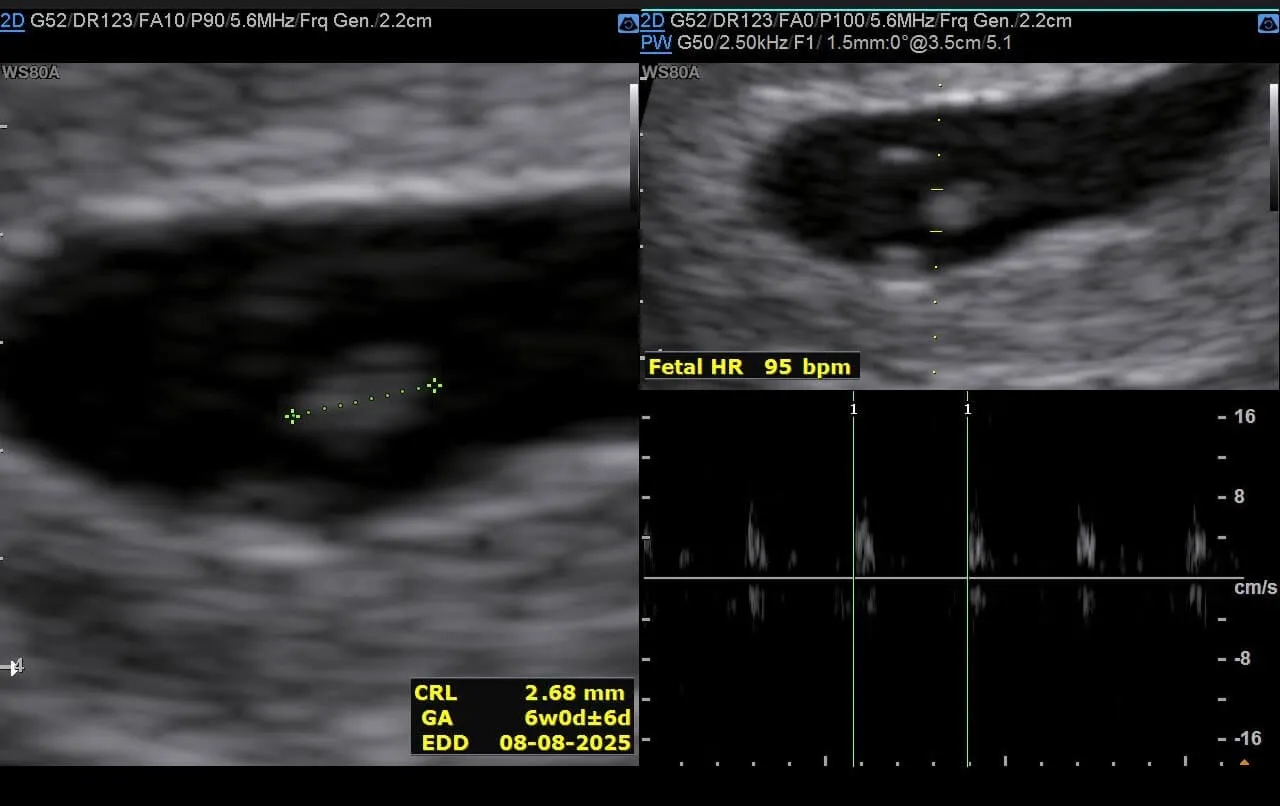

与此同时,我也亲眼见证了生命如何一点点成形:从一个 2mm、模糊不清的小点开始——

慢慢初具人形——